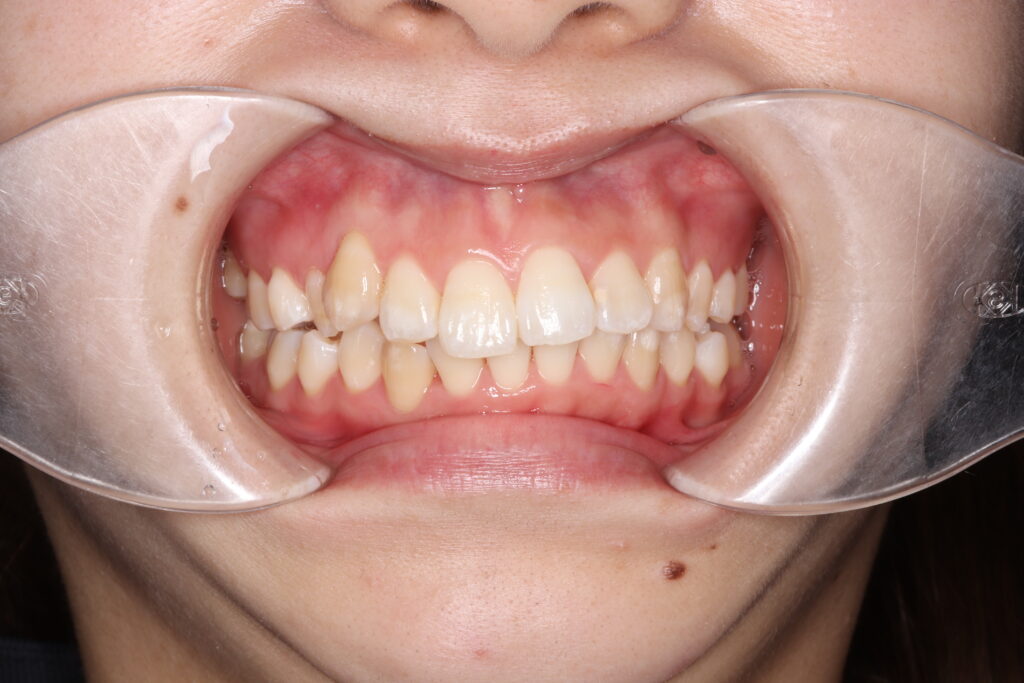

【部分矯正後の現在の歯並び】

こちらは部分矯正後の現在の歯並びの写真です。

部分矯正終了後は、社会人になったらいつか再度矯正治療を受けたい!そう考えながら日々を過ごしていました。当院のスタッフとして勤務していく中で、綺麗な歯並びになっていかれる患者様を見ていると、いつかは、、と思っていた矯正への気持ちが大きくなり、節目である30歳までに綺麗な歯並びになりたい!と思い今回ついに治療開始に踏み切りました!

この写真だけでも噛み合わせの悪さ、出っ歯が分かりやすく確認できますね😢